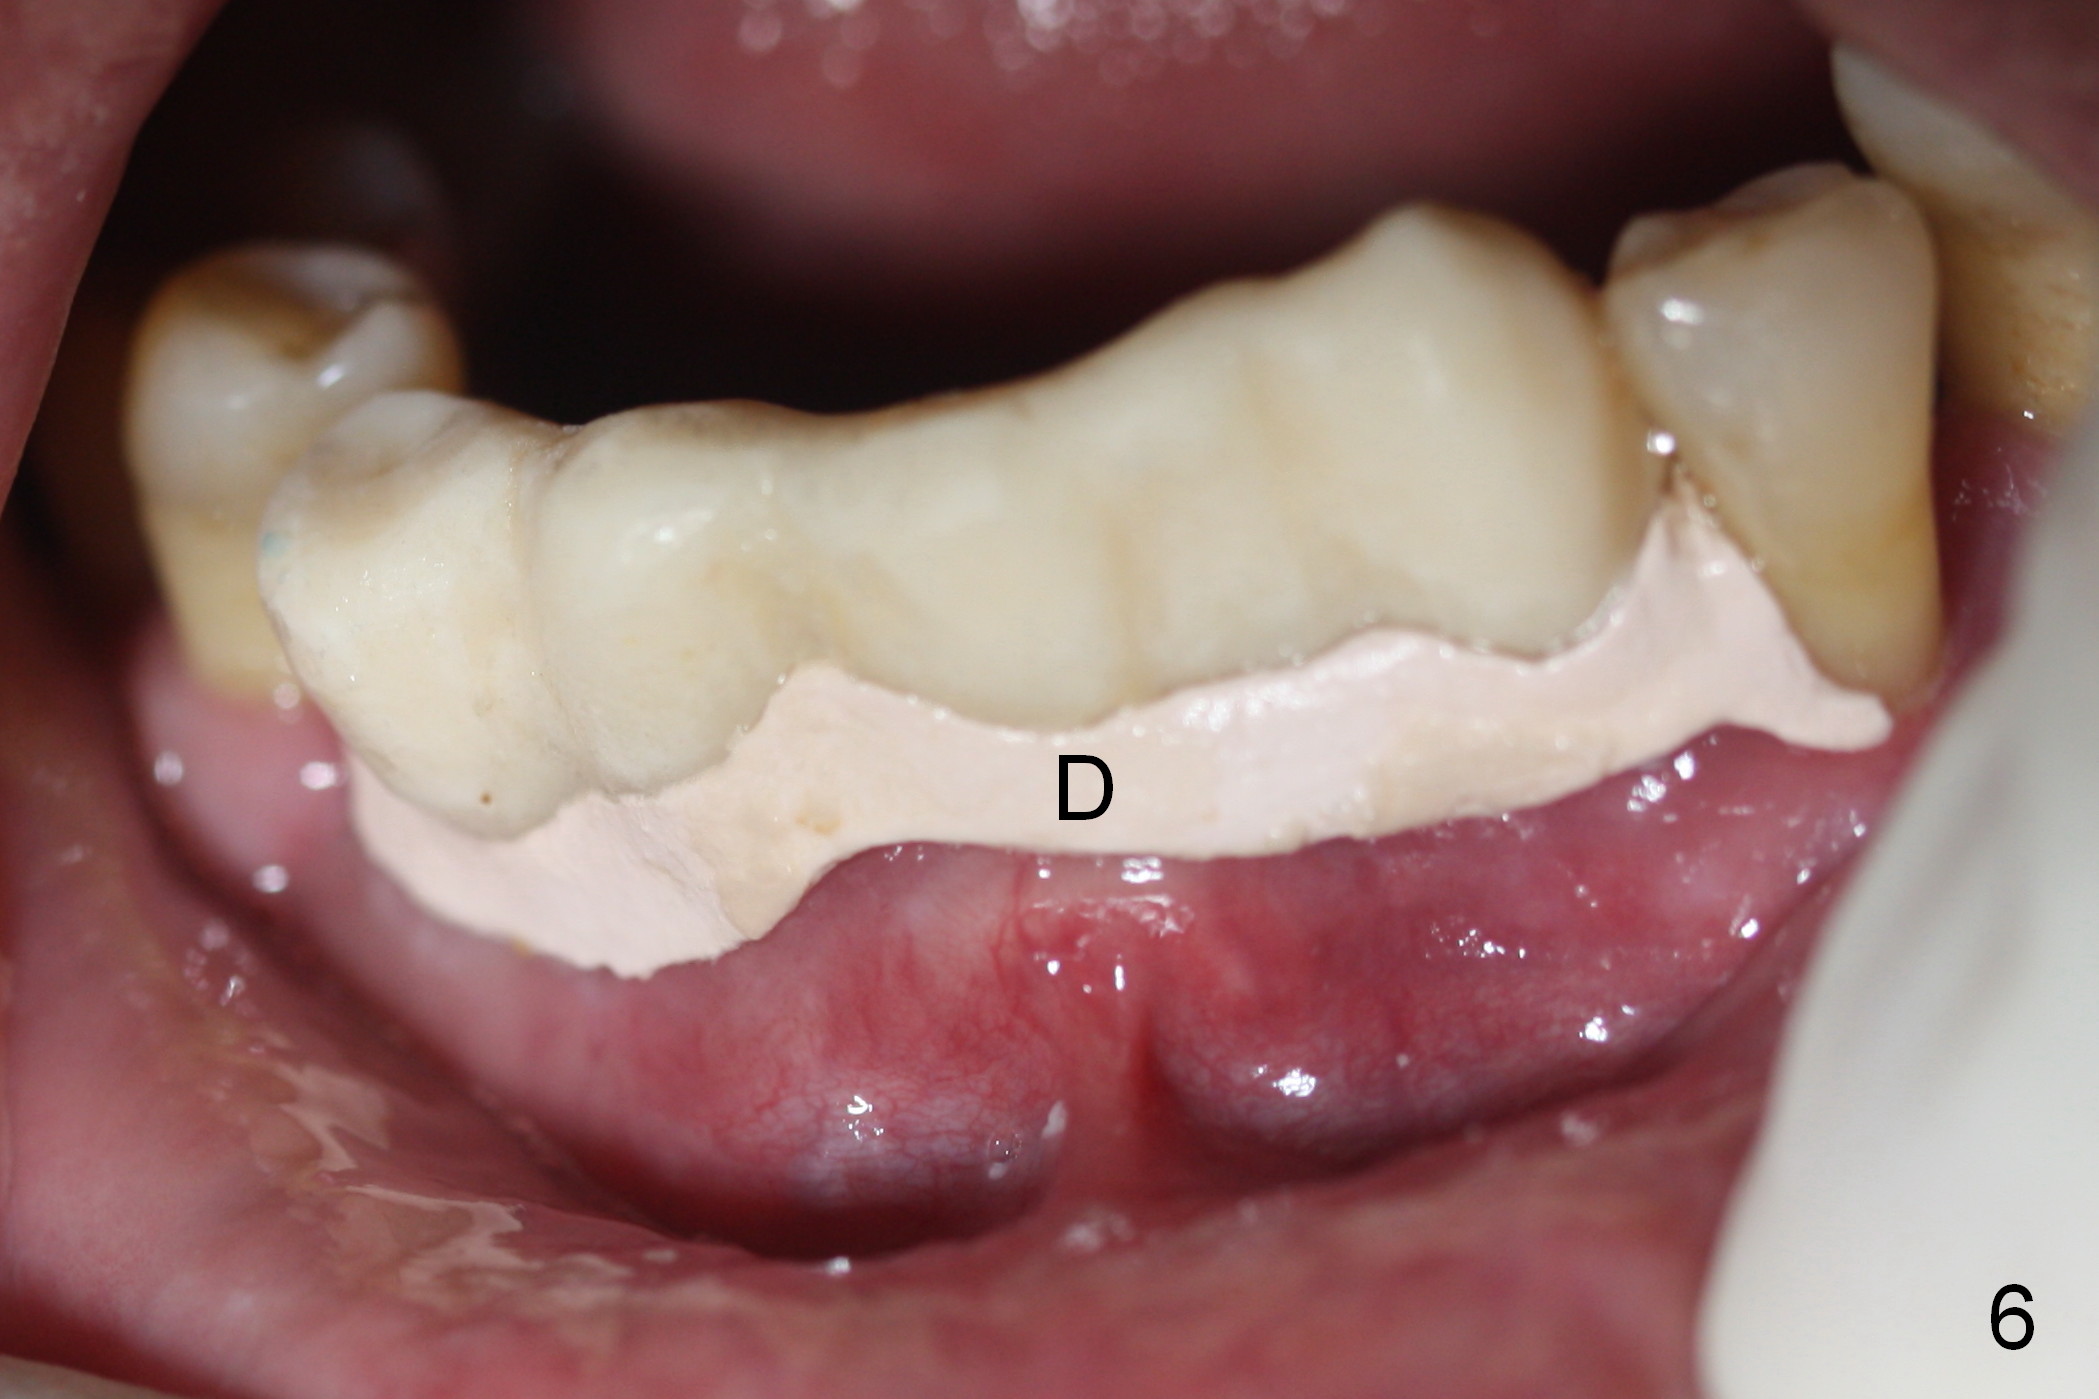

As expected, the bone density in the mandibular anterior region is found to be high during initial osteotomy (Fig.1-3).  Five implants are placed at the sites between #22 and 28 (Fig.4,5): 3x14(2) mm 1-piece (bone-level) implants in the incisor region; 4.5x17 mm 2-piece (tissue-level) ones in the canine/premolar area.  All of the implants are placed as lingual as possible.  Bone graft is placed (*).  Red dashed line: the superior border of the Inferior Alveolar Canal.  Immediate splinted provisional bridge is fabricated.  One week postop, periodontal dressing remains attached to the provisional and the gingiva.

The patient returns for restoration 4.5 months postop (Fig.7-9).  There appears bone growth around the implants.  Impression is taken together with the implants at #4 and 6.